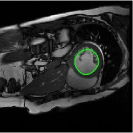

Fig. 4 displays the visual comparison results for segmenting eight brain tumor MR images between the RefLSM and three representative models: the RESLS [8765635], ALF[MA2019201], and L1 model[LIU2019193]. These images exhibit severe intensity inhomogeneity and noise attributable to inconsistent bias field and imaging equipment. The initial level set function (LSF) initialization was consistent across all models, as shown in Fig. 4 (a), which illustrates the initial placement of the zero level contour. For visual clarity, we included the ground truth in Fig. 4 (f). The segmentation outcomes from the RESLS, ALF, and L1 methods are presented in Fig. 4 (b), (c), and (d), respectively.

It is evident from the first and last columns of Fig. 4 (b) that the ALF model tends to become trapped in local minima under severe intensity inhomogeneity. Furthermore, segmentation results presented in the columns 1-4 of Fig. 4 (b) and (c) reveal that both the ALF and L1 models mistakenly segment small isolated or irrelevant regions due to the effects of irregular intensity patterns. Additionally, when weak boundaries are present, as seen in the 1st and 3rd columns of Fig. 4, the RESLS, ALF, and L1 methods fail to accurately identify object boundaries. Consequently, the zero level contours of these models deviate significantly from the objects throughout the level set evolution, causing drastic misalignment after further iterations.

In stark contrast, our proposed method exhibits greater robustness against images exhibiting severe intensity inhomogeneity and weak boundaries. The proposed prior constraint term effectively corrects for intensity inhomogeneity, while the proposed binary level set adeptly reduces noise during the segmentation process.